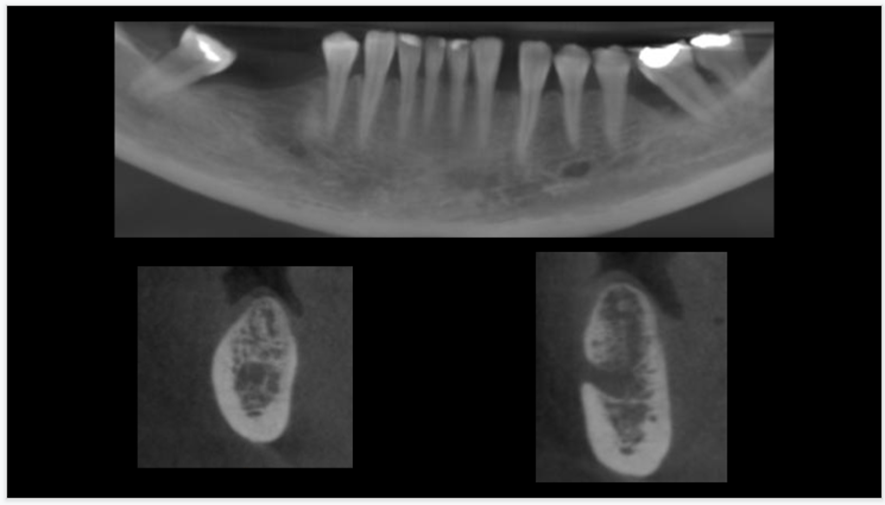

Neste caso clínico, a paciente C.X.M, sexo feminino, 46 anos, saudável, com histórico de doença periodontal, sem condições sistêmicas desfavoráveis e não-fumante, compareceu à clínica de especialização de Periodontia da UNIP. Após terapia periodontal, com a paciente apresentando saúde periodontal, foram instalados, na clínica de especialização, dois implantes do tipo HE, 4.0 X 6.0mm, Implacil De Bortoli. O acompanhamento deste caso clínico vem sendo realizado semestralmente na clínica de pós-graduação stricto sensu do programa de mestrado em Odontologia na área de Periodontia da UNIP, durante a terapia periodontal de suporte, nos últimos quatro anos.